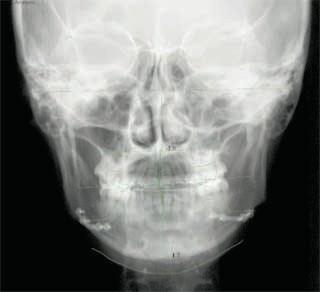

外科症例(アゴの輪郭でお悩みの方) 下顎前突

装置撤去です。動的処置は2年弱でしたので、通常のマルチブラケット治療とそれほど治療期間は変わりません。しかしながら、わずかな正中のズレが残ってしまいました。大きくは改善したのですが、左右のズレというものは、比較的、後戻りが現れやすい問題です。筋肉の影響によるものや、咬合平面の傾斜が左右的に水平でない事などが関係しているような気がします。今後は保定治療に移行し、数年にわたって咬合の安定状態を管理していきます。